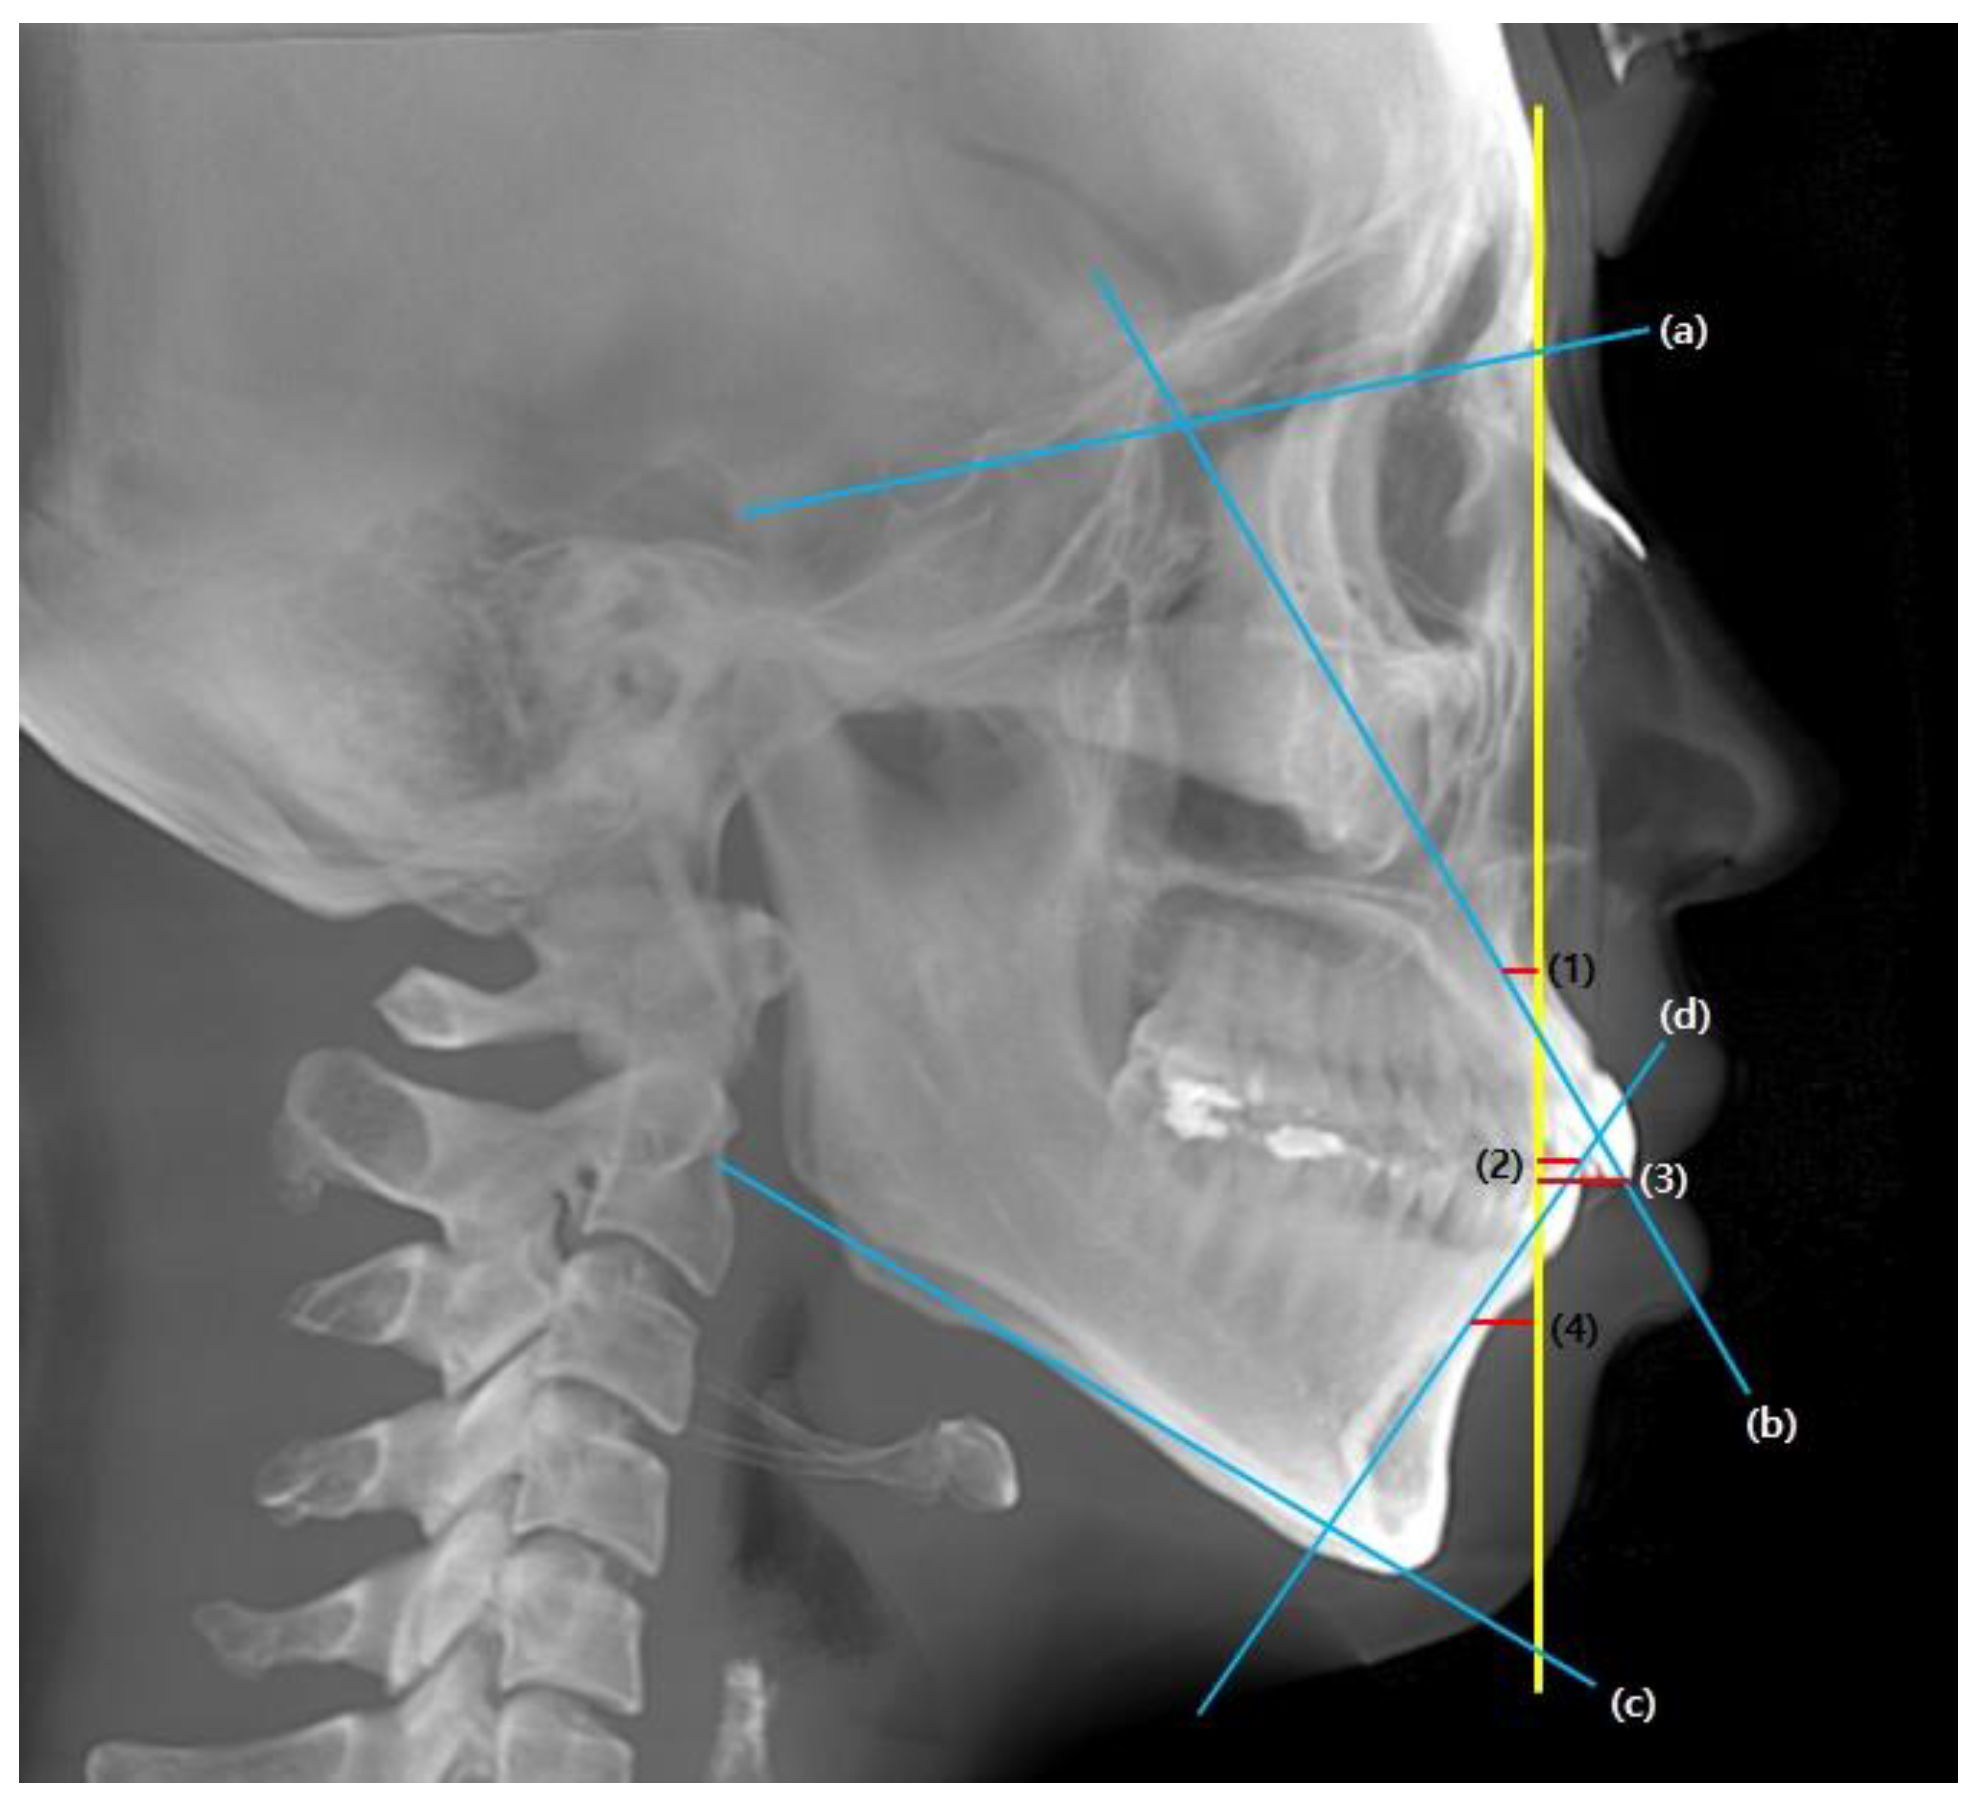

For the pre-treatment (T0) and post-treatment (T1) CBCT images, a coordinate system with the Frankfort horizontal plane parallel to the xy-plane, the line connecting the orbitale parallel to the x-axis, and the pogonion being set as the zero point was followed. CBCT cephalograms were synthesized from the reoriented CBCT data, and linear measurements were performed using the OnDemand3D software (Cybermed, Seoul, Korea) (Figure 1). To determine the total distance of the incisor movement, a vertical reference line (vert T) constructed through a stable craniofacial structure was used to measure the distance between the incisal tip and root apex between T0 and T1 (Figure 2).

Figure 1. (A), CBCT 3D image view. The image was oriented along the Frankfort horizontal plane in reference to the right porion, right orbitale, and left orbitale. (B), CBCT-synthesized lateral cephalogram was constructed in accordance with orientation.